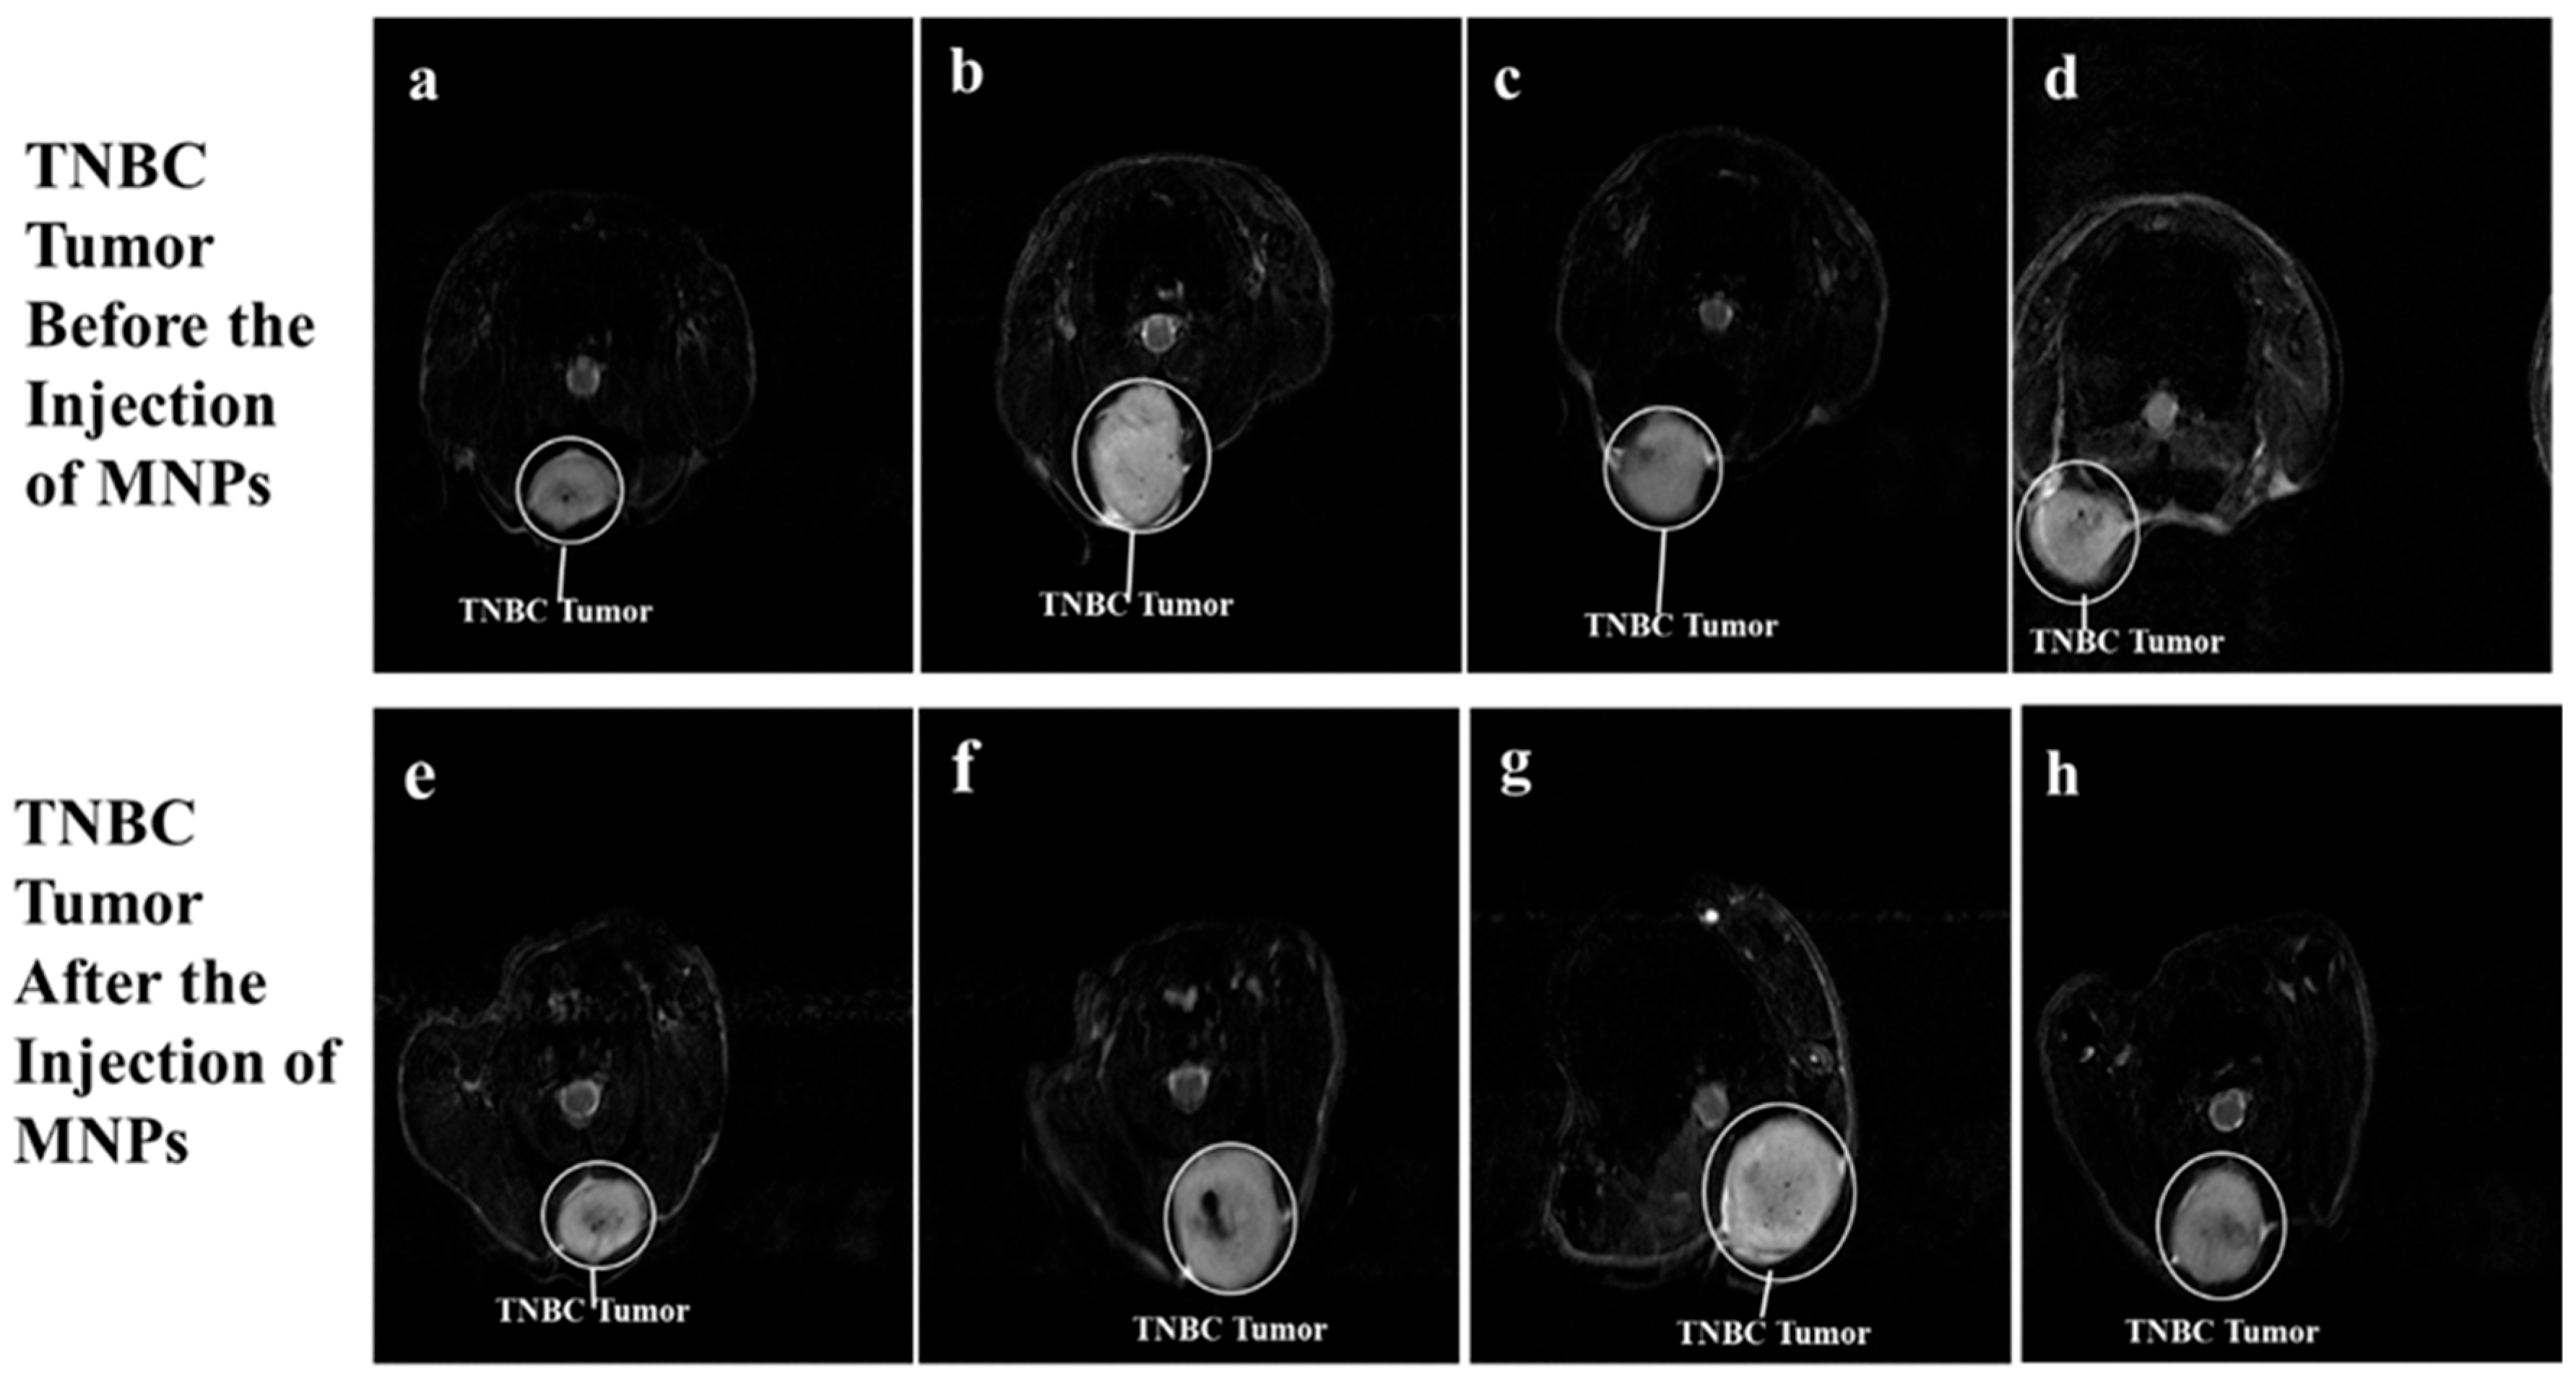

Figure 5a–h show sectional dorsal views of mice induced with TNBC tumors on the trunk. The TNBC tumor appears as a white colored, irregularly shaped tumor. The T2-weighted 7T MRI scans of the TNBC tumors in Figure 5e, Figure 5f, Figure 5g, and Figure 5h appear darker, with traces of dark colorations on the TNBC tumor, 2 h post-injection of BMNR, LCMNR, BSSMNP, and LCSSMNP, respectively.

Figure 5. T2-weighted 7 Tesla MRI scans. (ah) 7 Tesla MRI scans of TNBC tumors induced in nude mice. (e) is the 7 Tesla MRI scan of the TNBC tumor shown in (a) 2 h after the mice were injected with BMNR. (f) is the 7 Tesla MRI scan of the TNBC tumor shown in (b) 2 h after the mice were injected with LCMNR. (g) is the 7 Tesla MRI scan of the TNBC tumor shown in (c) 2 h after the mice were injected with BSSMNP. (h) is the 7 Tesla MRI scan of the TNBC tumor shown in (d) 2 h after the mice were injected with LCSSMNP.